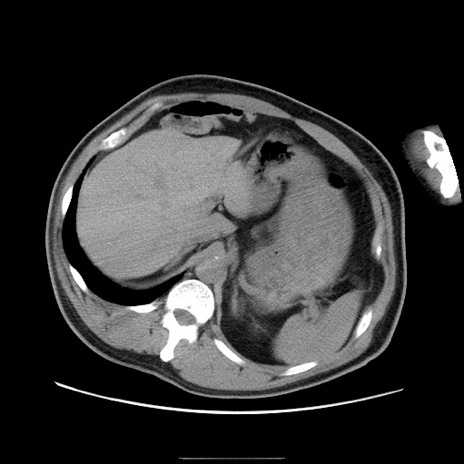

症例22(横断像)

【症例】50歳代男性

【主訴】腹痛

【現病歴】AVMからの被殻出血のため回復期リハ病棟入院中。 本日午後3時頃急に下腹部痛が出現した。

【既往歴】AVM、被殻出血、虫垂炎、高血圧

【身体所見】意識晴明、左半身不全麻痺、会話の理解は良好、36.5°C、腹部:膨隆、全体に板状硬、下腹部正中に圧痛点あり、反跳痛-、筋性防御不明、右下腹部にope scar

【データ】WBC 9400、CRP 0.06